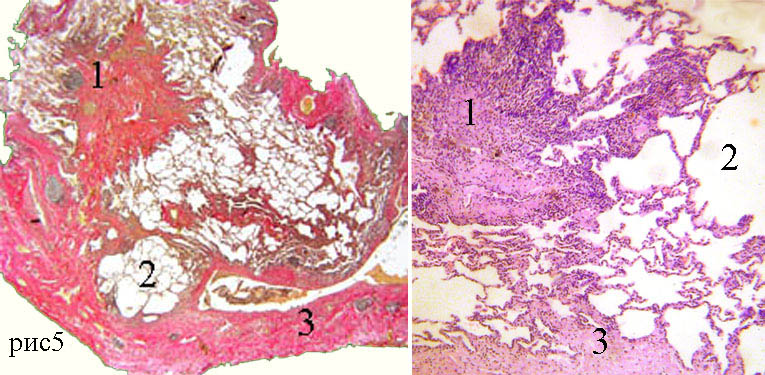

Карнификация Легкого: Микропрепараты и Диагностика

Раздел: Калейдоскоп образов